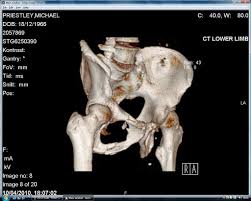

고관절 통증이 나타나는 위치

고관절 통증은 엉덩이 깊숙한 부위에서만 느껴진다고 생각하기 쉽지만, 실제로는 다양한 위치로 퍼져 나타날 수 있습니다.

특히 사타구니 통증은 고관절 이상을 가장 강하게 의심할 수 있는 신호로 전문가들도 중요하게 보는 증상입니다.